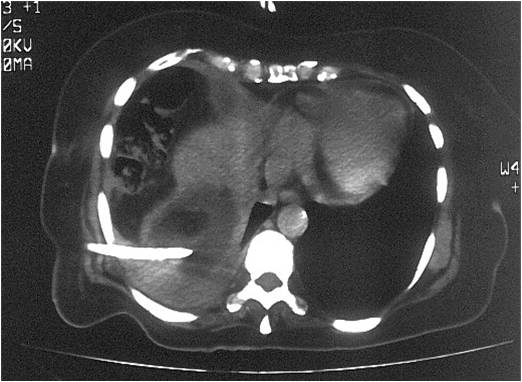

- Successful placement in sub-hepatic abscess post right hemicolectomy